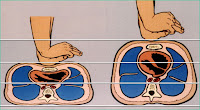

4ta Maniobra De Leopold:

Maniobra

del Grado de encajamiento de la presentación. Buscamos el grado de encajamiento

de la parte fetal que se ofrece al estrecho superior de la pelvis materna,

puede ser de 4 grados para la presentación cefálica, lo cual no se cumple para

la presentación podálica o pelviana:

1: Alta y

móvil, 2: Insinuada o Fija, 3: Encajada y 4: Muy encajada.(Vea el video aquí)

_ Alta y

móvil, cuando la circunferencia cefálica y/o la coronilla se encuentran por

encima del estrecho superior de la pelvis materna y se puede hacer peloteo.

_

Insinuada, cuando la circunferencia cefálica se encuentran a nivel del estrecho

superior de la pelvis materna y no se puede hacer peloteo.

_

Encajada, cuando la circunferencia cefálica se encuentran por debajo del

estrecho superior de la pelvis materna, y al tratar de palpar con ambas manos

por encima y detrás de la sínfisis del pubis, encontramos un vacío.

_ Muy

encajada, cuando la circunferencia cefálica se encuentran muy por debajo del

estrecho superior de la pelvis materna, y al tratar de palpar con ambas manos

por encima de la sínfisis del pubis, encontramos los hombros fetales en sentido

anteroposterior.

Técnica

El

examinador se sitúa del lado derecho de la paciente, pero de espalda a ella,

mirando a sus pies. Con la punta de los dedos profundiza hacia la pelvis por

encima del pubis, precisando el grado de encajamiento de la presentación.

Intentará apreciar con las puntas de los dedos si se trata de la cabeza o las

nalgas, y si la presentación se encuentra móvil o fija. Se puede corroborar,

además, si el dorso es derecho o izquierdo, ya que la parte más prominente es

la frente y la más remota es el occipucio. Además, podemos plantear el grado de

flexión en la presentación cefálica, porque si la frente está más alta que el

occipucio debe estar la cabeza flexionada; si están más o menos al mismo nivel,

debe ser un sincipucio, y si el occipucio está más alto que la frente, debe

tener algún grado de deflexión.